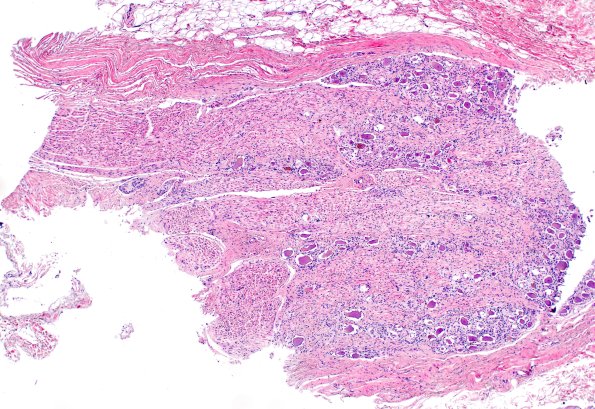

Perineurioma, Intraneural

17A1 (Case 17) control DRG H&E 4X

17A1,2 A lumbosacral DRG at low (4X) and higher (20X) magnification. (H&E)